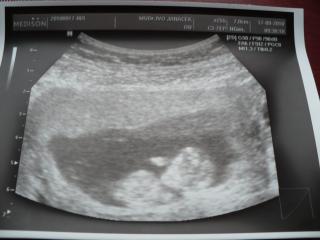

Ahojky holky, tak jsme po kontrole 11+2 - dvě ruce s prstíky, dvě nohy, jedna hlava, srdíčko a prý dostatečné množství plodové vody (dokážete si představit, že tato informace byla pro mně asi nejdůležitější, že🙂).TP 6.dubna 😀 Tak ještě aby ten pondělní screening dopadl stejně....Přikládám fotečku.

@breberuska breber nadhera, hrozne ti to preju a uprimne se mi zatraslo srdicko... jsi takova nase predloha a vsechny ti to hrozne prejeme, zaslouzis si to a vsechny te moc chceme nasledovat. nejkrasnejsi obrazek dne!!! hodne stesti!!!